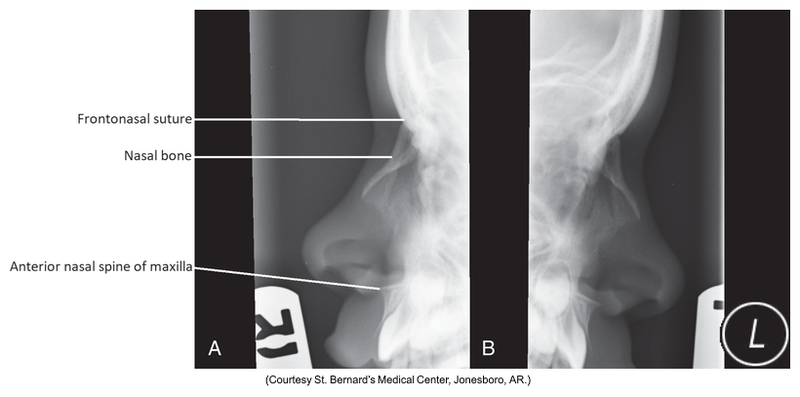

Lateral Projection of the nasal bones

Lateral of nasal bones